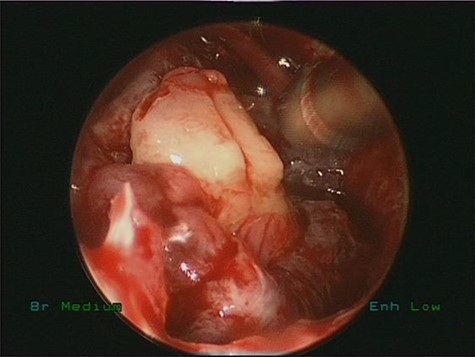

Intraoperative, the right middle meatus was full of frank pus (Fig. 2) which was drained. Endoscopic middle meatus antrostomies was performed and a bilateral big cystic masses completely filling both maxillary sinus were visualized along with a tooth impacted in the medial wall of the right maxillary sinus obstructing the natural drainage. The diagnosis of bilateral dentigerous cysts with ectopic teeth was made on clinical and radiographic findings.

Intraoperative endoscopic view of frank pus draining the right maxillary sinus